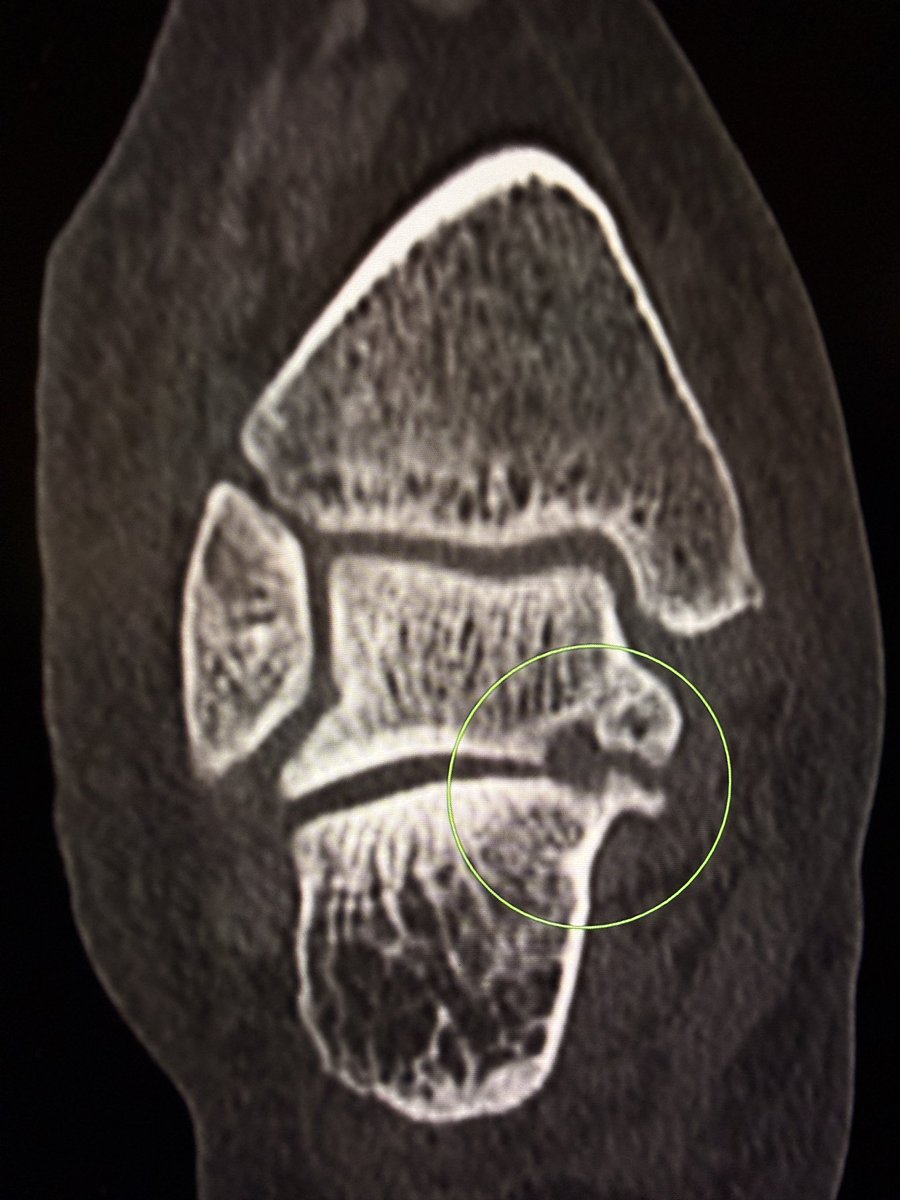

Talar beak is a marker of restricted subtalar motion, not a diagnosis. In a young patient, actively search for a subtalar coalition.

This case showed a fibrous coalition of Medial accessory talocalcaneal articulation at the level of the posterior sustentaculum tali, between the Talus and Calcaneus.

Wisdom: A talar beak should trigger a search, not end it.